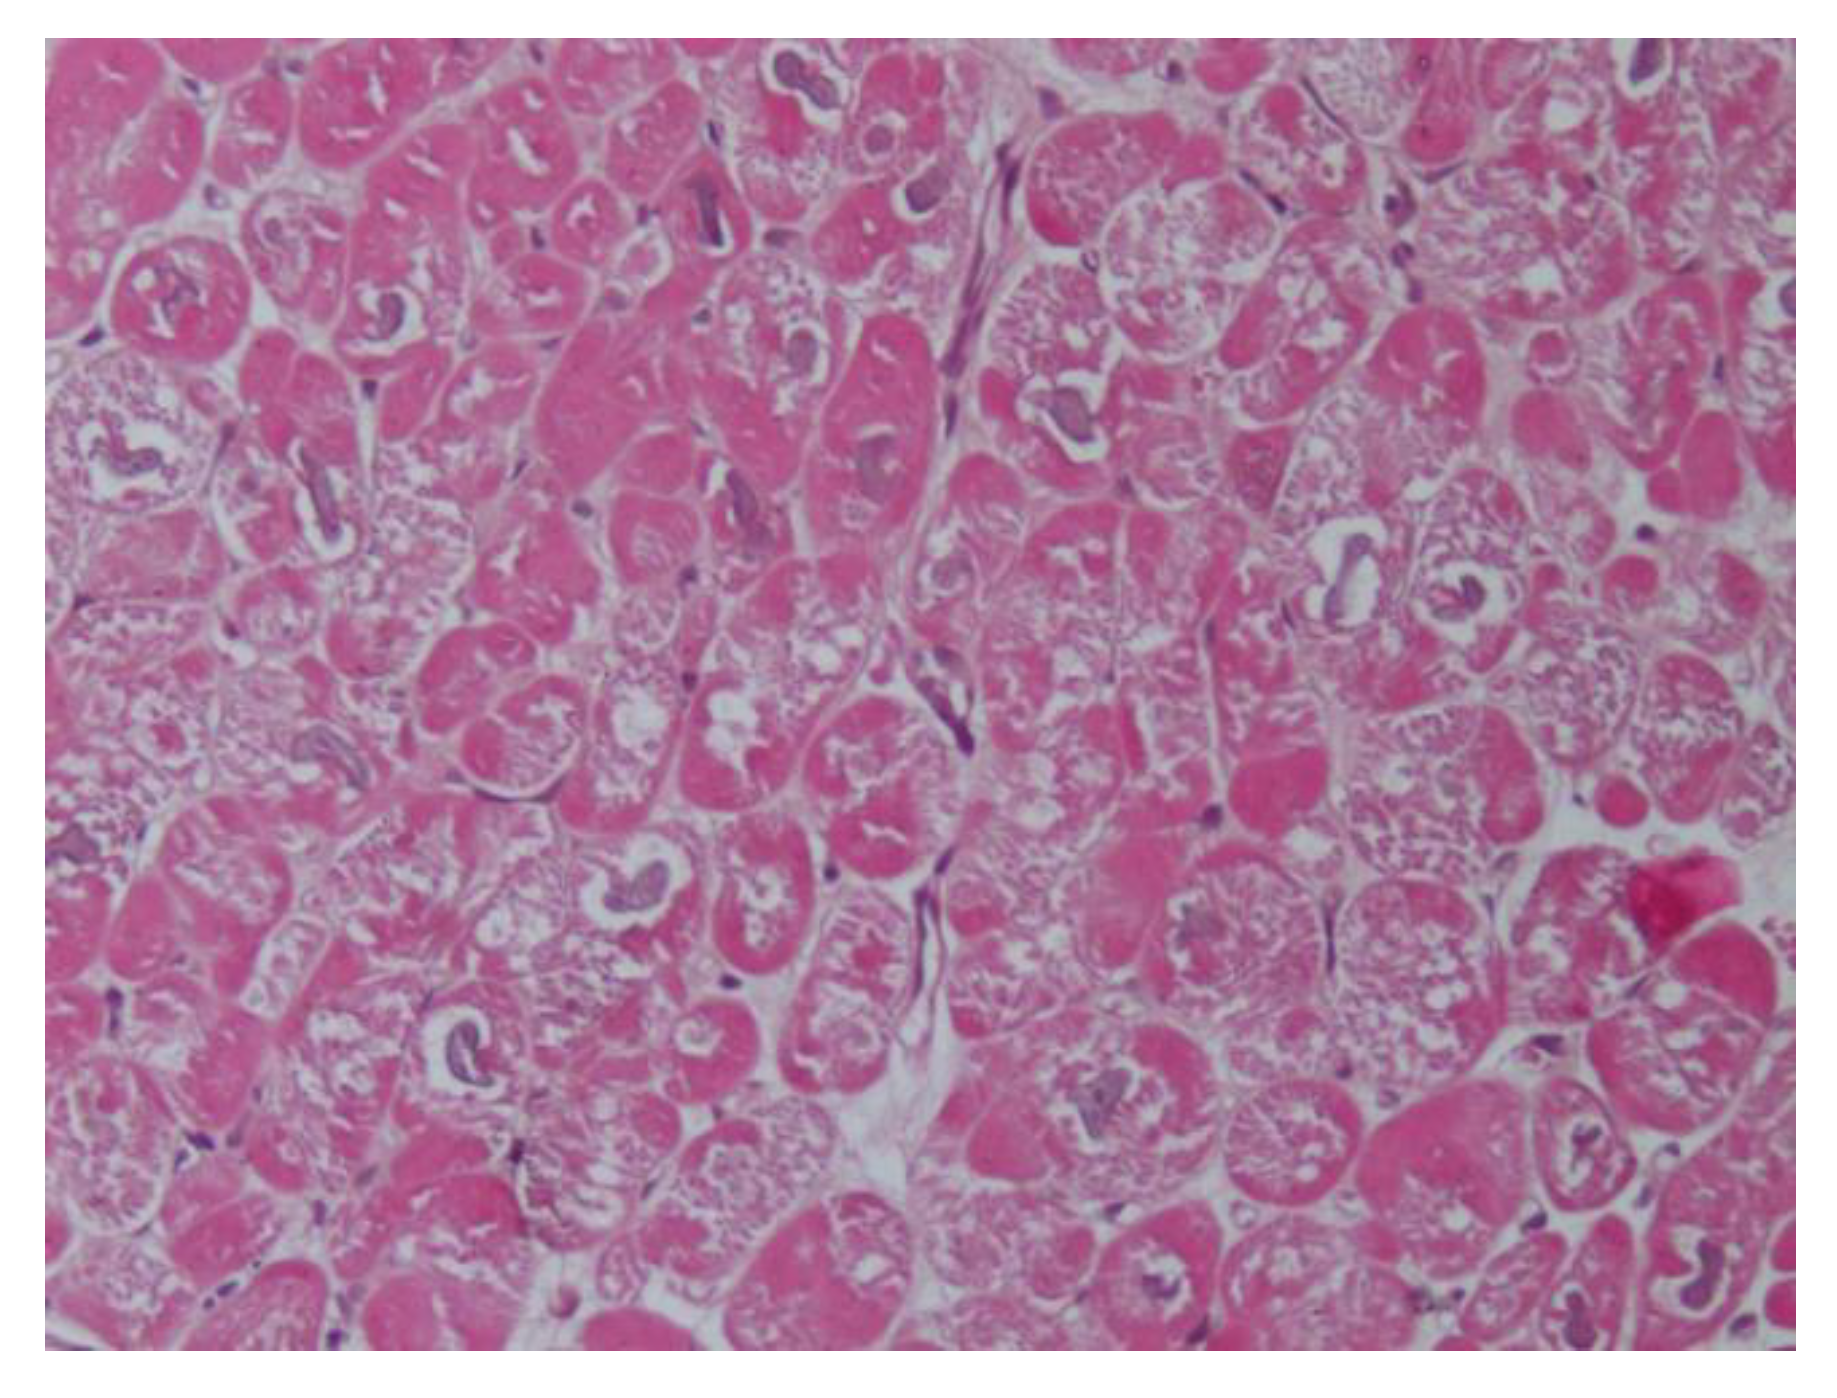

In the literature, cardiovascular damage induced by sympatho-mimetic amines has been well described. Microscopically, the first insult is diffuse edema and a modest loss of striations in cardiomyocytes, and subsequently foci of myocardial cellular necrosis can be found [50]. Interestingly, in cocaine abuse, we observe similar mechanisms of the damage of myocardial toxicity, caused by an inappropriate endogenous hypercatecholaminergic secretion. These features include marked oxidative stress and mitochondrial dysfunction. The chronic use of cocaine determines various degrees of systolic and diastolic dysfunction, cardiac hypertrophy, and dilation [51]. Histologically, it is possible to observe the loss of myofibrils, multiple foci of band contractions, and fibrosis [52].

We previously described a case report of a 37-year-old woman presenting with an history of dyspnea, chest pain, palpitation, and hypertension [55]. Electrocardiogram, echocardiogram, and cardiac magnetic resonance showed severe LVH with a prevalent involvement of the anterior portion of the interventricular septum. EMB demonstrated features of the hypercontraction of myofilaments with the formation of contraction bands and occasional cellular necrosis and wide and perivascular fibrosis. Electron microscopy at higher magnifications showed the catecholamine-induced diffuse contraction with band necrosis. Finally, we found a rare cases of catecholamine-induced CMPs due to adrenal adenoma mixed with nodules enriched in epinephrine-type secreting granules (Figure 3).

Figure 3. Hematoxylin and eosin staining (200×) shows the hypercontraction of sarcomeres with contraction band necrosis and lymphocytic infiltration due to catecholamine overproduction from pheochromocytoma.